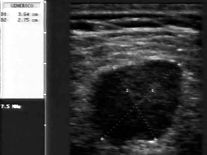

Commento all'esame: ematoma organizzato sottocutaneo dopo intervento per laparocele.

Conclusioni: ematoma organizzato sottocutaneo (subcutaneous organized hematoma).